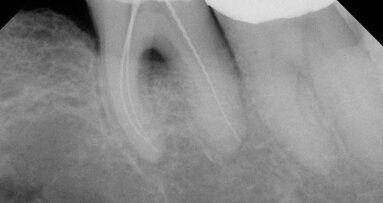

During the 1990s, computer technology gradually replaced hard copy paper records for patients, and scheduling became a more routine process. The influence of computers in the advancement of endodontics was incredible! Many in our profession today don’t remember the “darkroom,” the small, closet-like room in our offices where the developing and fixing of radiograph films was done. One of the most profound changes in dental technology was the advent of digital radiography. Cone-beam computed tomography (CBCT) became a huge asset for a better diagnosis, easier treatment and more predictable results. MTA was introduced as a new root-end filling material and to be used for perforation repairs.

At the turn of the century, changes had become the norm. More predictable treatments for invasive cervical resorption (ICR) were established. The minimally invasive technique for maintaining root structure and strength during conventional treatment was adopted. New bioceramic materials and sealers were developed. The GentleWave technique is one of the more recent developments to aid in the conventional cleaning and disinfection of the canal system.